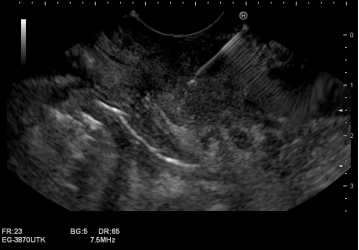

技术实施:毫米级精准操作,一站完成诊断与治疗

在充分的术前准备和家属沟通后,手术如期进行。精准诊断阶段:消化内科温蕾医生首先进行EUS检查。内镜前端的高频超声探头紧贴消化道壁,对胰头部病灶进行了360度无死角扫描,清晰地显示了肿瘤的大小、边界及其与周围血管的毗邻关系。在实时超声的精确引导下,穿刺针犹如“GPS导航”般,毫厘不差地穿越十二指肠壁,直达肿瘤核心,成功获取了足量的条索状组织,为病理诊断奠定了坚实基础。紧急治疗阶段:随后,无缝切换至ERCP操作。蒋承志医生熟练地把十二指肠镜抵达十二指肠乳头,造影清晰显示肝外胆管重度狭窄。导丝顺利通过狭窄段,一枚覆膜金属支架被精准释放于梗阻部位。瞬间,淤积的胆汁得以顺畅流入肠道,梗阻成功解除。整个手术过程流畅,患者无特殊不适。术后病理结合免疫组化,迅速明确诊断为胰腺导管腺癌。随着支架起效,患者黄疸快速消退,肝功能指标显著改善,为后续可能进行的抗肿瘤治疗赢得了宝贵时间和身体条件。